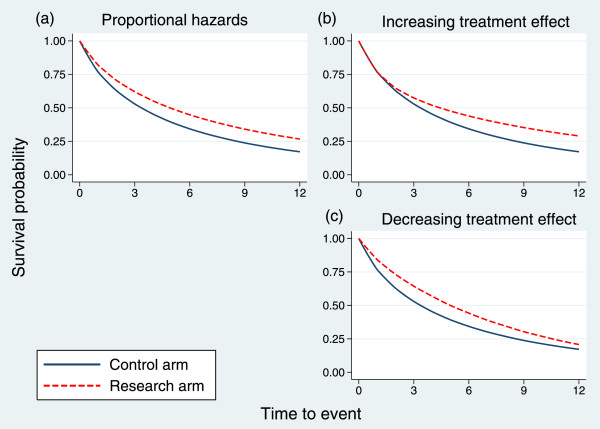

Times to event were simulated under piecewise exponential models according to two patterns of non-proportional hazards, HR 1(t) and HR 2(t), representing increasing or decreasing treatment effects, respectively. The relevant design parameters are shown in Table 3. For example, S0(t)=0.767 at t=1 yr means that the control arm survival probability is 0.767 at t=1. The HR for the increasing treatment effect (HR 1) is 1.00 in the interval t∈(0,1), and so the survival probability in the research arm would also be 0.767 at t=1. The pattern of the survival curves for PH and for the two non-PH cases is shown in Figure 3.

Figure 3.

Survival curves in the control and research arms for three hazard ratio patterns. (a) Proportional hazards; (b) increasing treatment effect; (c) decreasing treatment effect.

The simulation was performed with 5,000 replicates. The results are shown in Table 4. Under both patterns of non-PH, the joint test outperforms the logrank test, markedly so when the treatment effect increases with time. Under PH, the power of the joint test is of course lower.